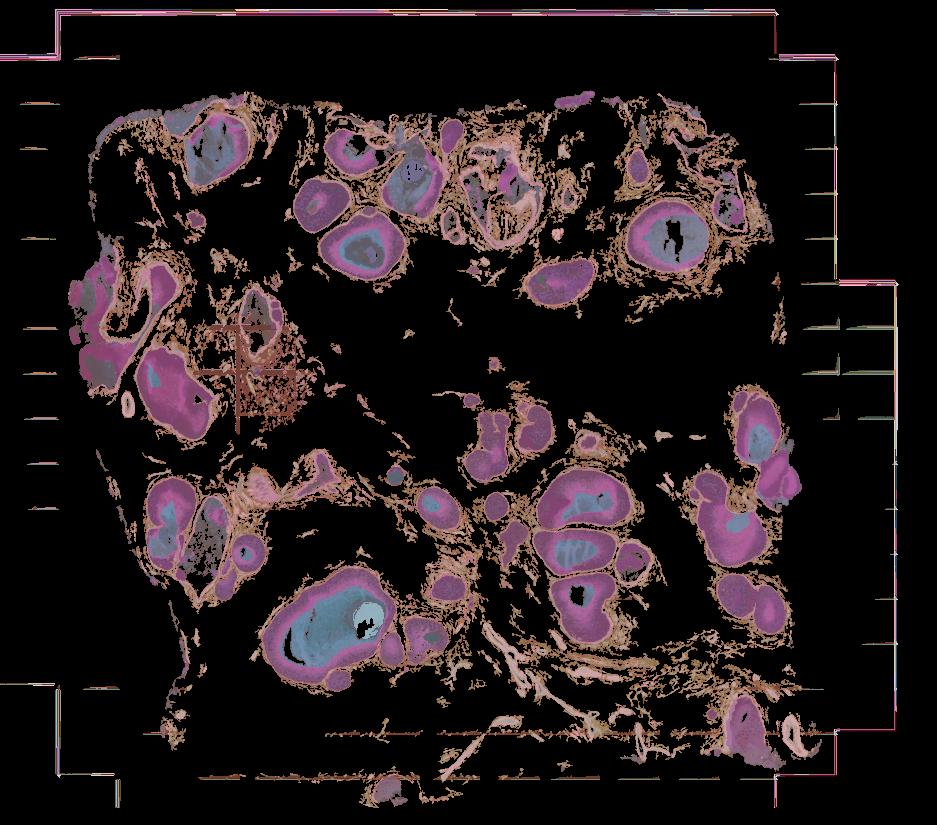

To study the spatial interactions among cancer and non-cancer cells1, we here examined a cohort of 131 tumour sections from 78 cases across 6 cancer types by Visium spatial transcriptomics (ST). This was combined with 48 matched single-nucleus RNA sequencing samples and 22 matched co-detection by indexing (CODEX) samples. To describe tumour structures and habitats, we defined ‘tumour microregions’ as spatially distinct cancer cell clusters separated by stromal components. They varied in size and density among cancer types, with the largest microregions observed in metastatic samples. We further grouped microregions with shared genetic alterations into ‘spatial subclones’. Thirty five tumour sections exhibited subclonal structures. Spatial subclones with distinct copy number variations and mutations displayed differential oncogenic activities. We identified increased metabolic activity at the centre and increased antigen presentation along the leading edges of microregions. We also observed variable T cell infiltrations within microregions and macrophages predominantly residing at tumour boundaries. We reconstructed 3D tumour structures by co-registering 48 serial ST sections from 16 samples, which provided insights into the spatial organization and heterogeneity of tumours. Additionally, using an unsupervised deep-learning algorithm and integrating ST and CODEX data, we identified both immune hot and cold neighbourhoods and enhanced immune exhaustion markers surrounding the 3D subclones. These findings contribute to the understanding of spatial tumour evolution through interactions with the local microenvironment in 2D and 3D space, providing valuable insights into tumour biology.